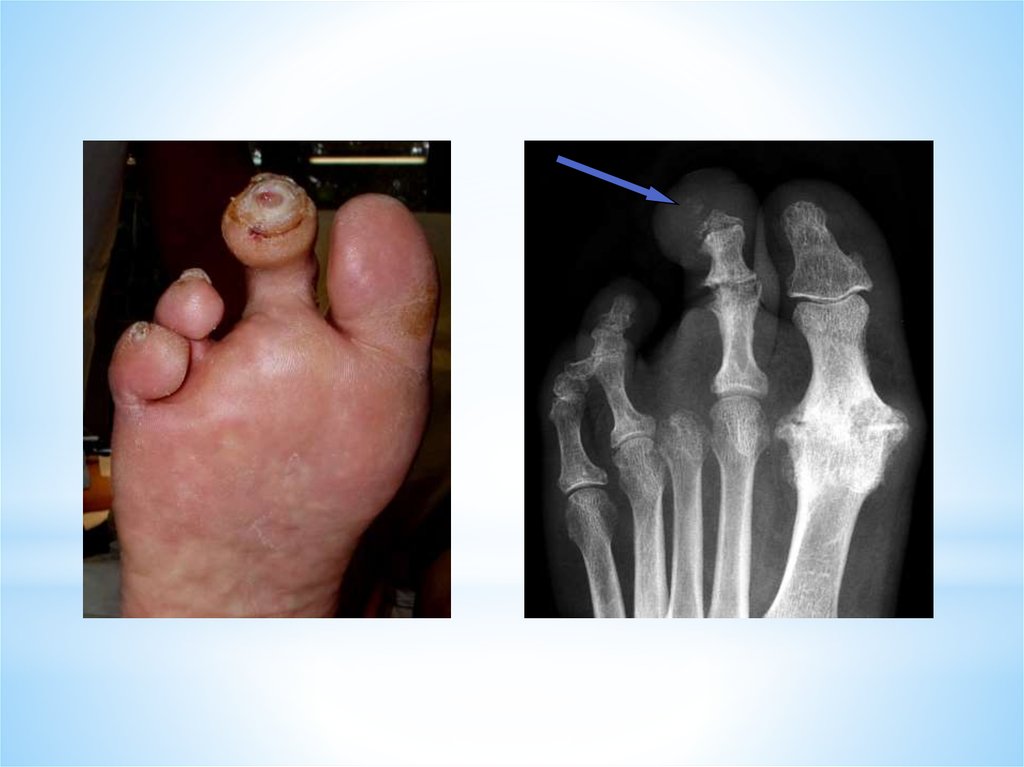

Остеомиелит развился на фоне трофических язв в

дистальных отделах стопы

Диагностика остеомиелита:

*рентгенологическое исследование (до операции)

*гистологическое исследование (после операции)